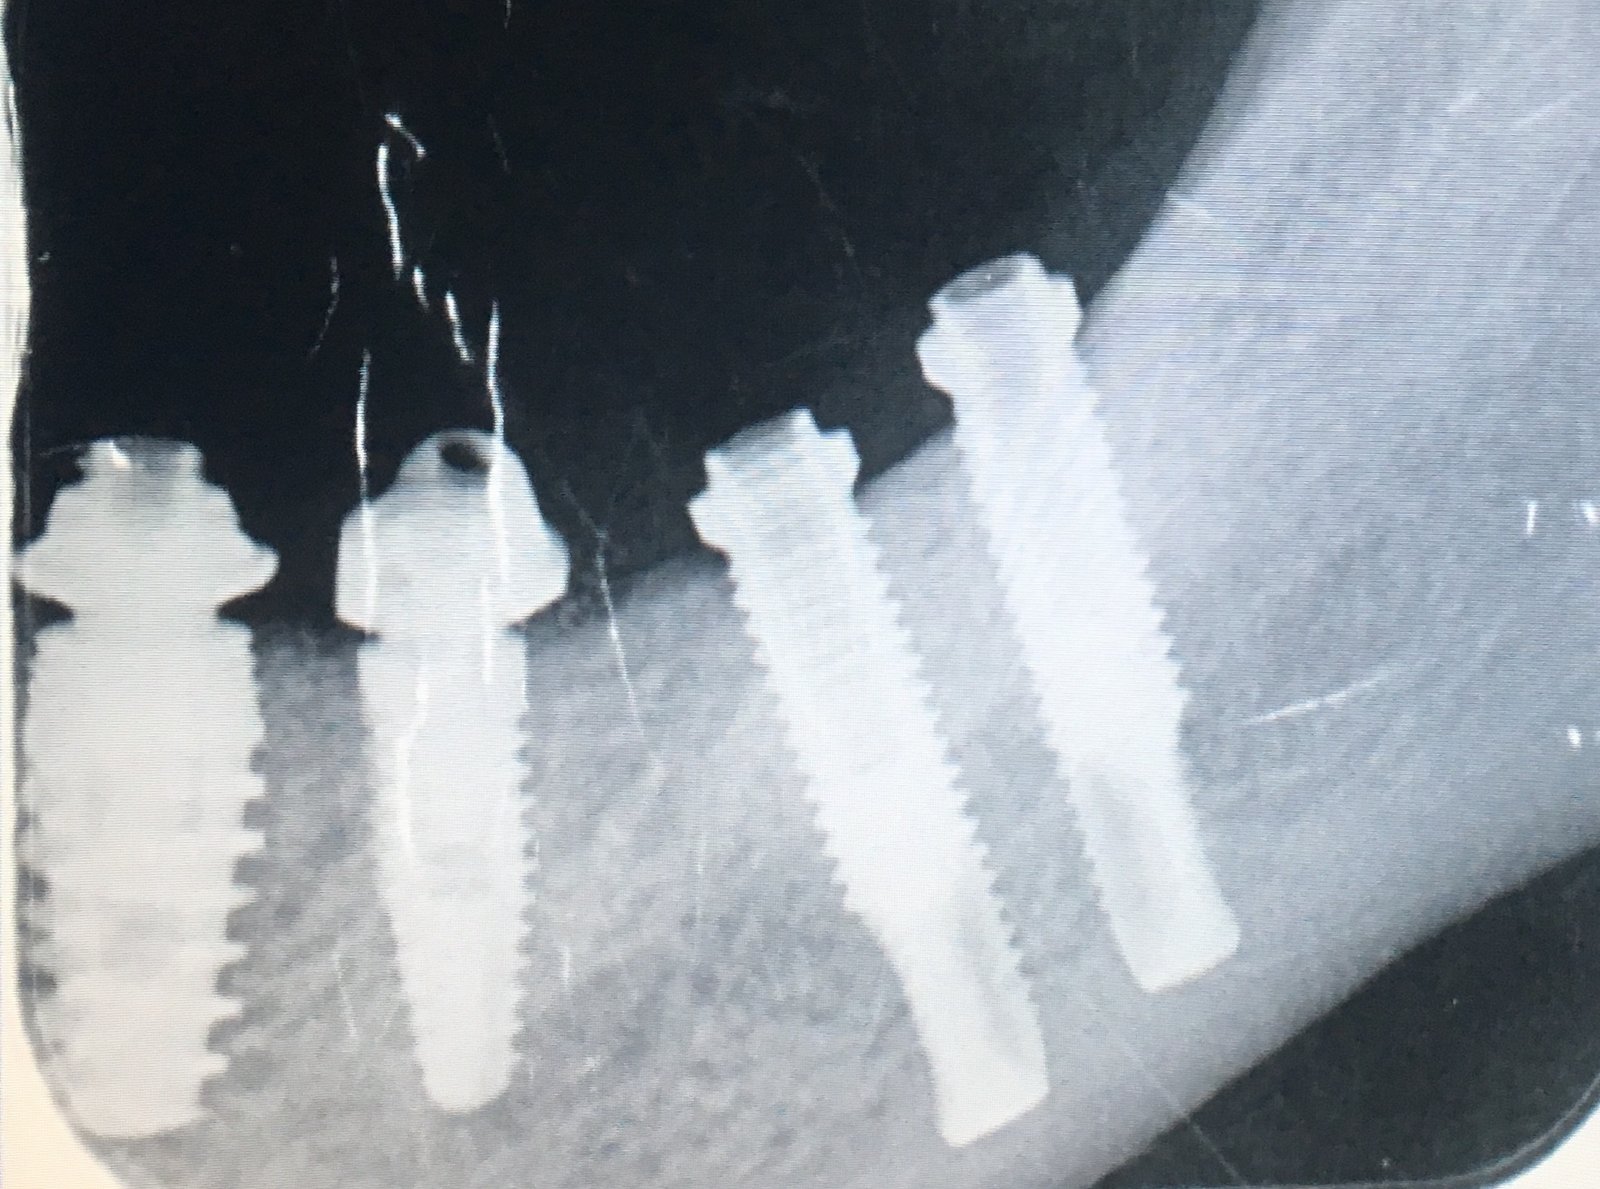

Buenas tardes, Paciente acude a la clínica para rehabilitar los 4 implantes que se observan en la fotografía, con los 2 mesiales no hay problema. Pero los distales han sido [...]

Colocados hace 8 años.....